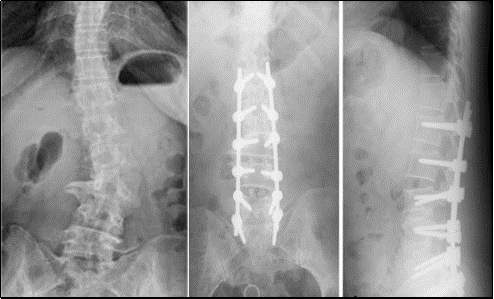

后路椎管减压+长节段固定,在后路椎管减压的基础上,行长节段固定,可以彻底纠正畸形,但手术切口长、创伤大,老年人耐受性差、骨质疏松,容易出现术后并发症。

微创OLIF手术,通过微创孔道,植入椎间融合器,间接减压、纠正侧弯,必要时辅助后路经皮固定,创伤小、恢复快、病人术后早期下地行走,值得提倡。